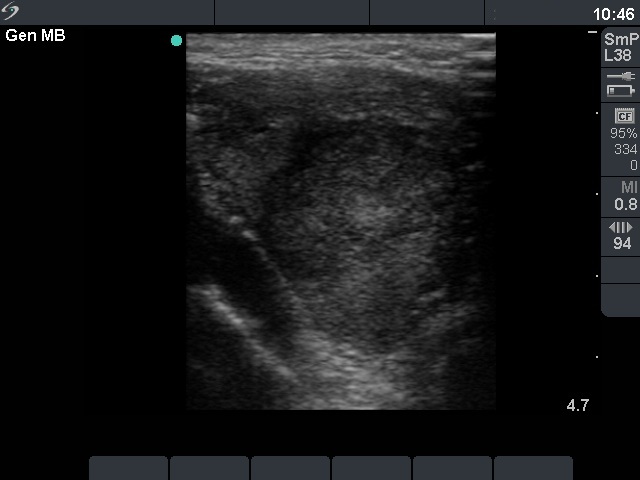

Ultrasonography. There was a large hypoechogenic nodule with irregular borders in the right thyroid. The vascularization was decreased.